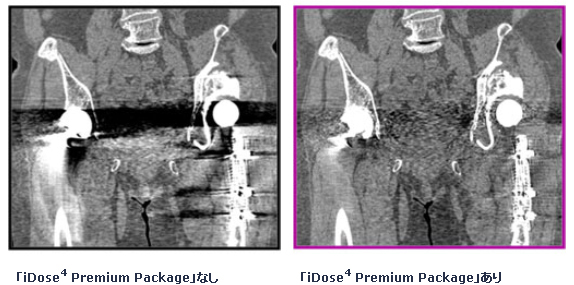

昨年10月にAuntMinnie(世界最大規模の放射線科情報ウェブサイト)よりBest New Radiology Softwareとして表彰を受けた逐次近似応用再構成である「iDose4 Premium Package」(アイドーズ フォー プレミアム パッケージ)を標準搭載し、低被ばくと高画質を高いレベルで実現します。また金属アーチファクトを抑制する技術により、整形インプラント周辺の組織に対する視認性が高まり、診断をより効果的にサポートします。昨年北米放射線学会(RSNA2012)で発表をしたシステムモデル逐次近似再構成技術である「IMR」(アイエムアール)をオプション搭載することも可能です。